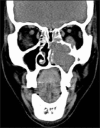

Inflammatory myofibroblastic tumor (IMT) is a rare tumor of uncertain origin with variable biological behavior ranging from reactive lesions to highly aggressive malignancy. Oral IMTs are extremely rare and only 25 cases had been reported so far. A case of IMT with sarcomatous transformation in an extraction site with a history of tooth extraction following tooth mobility of an upper left molar tooth is presented here. The tooth was extracted following a complaint of gingival swelling and mobility of tooth. Though malignant transformation in IMTs had been documented in the extra oral sites, wide search of associated literature suggests, this is the first case of oral IMT showing malignant change associated with gingiva. The case report attempts to highlight the variant possibilities of tooth mobility other than periodontitis and the importance of assessing the primary cause of such conditions.